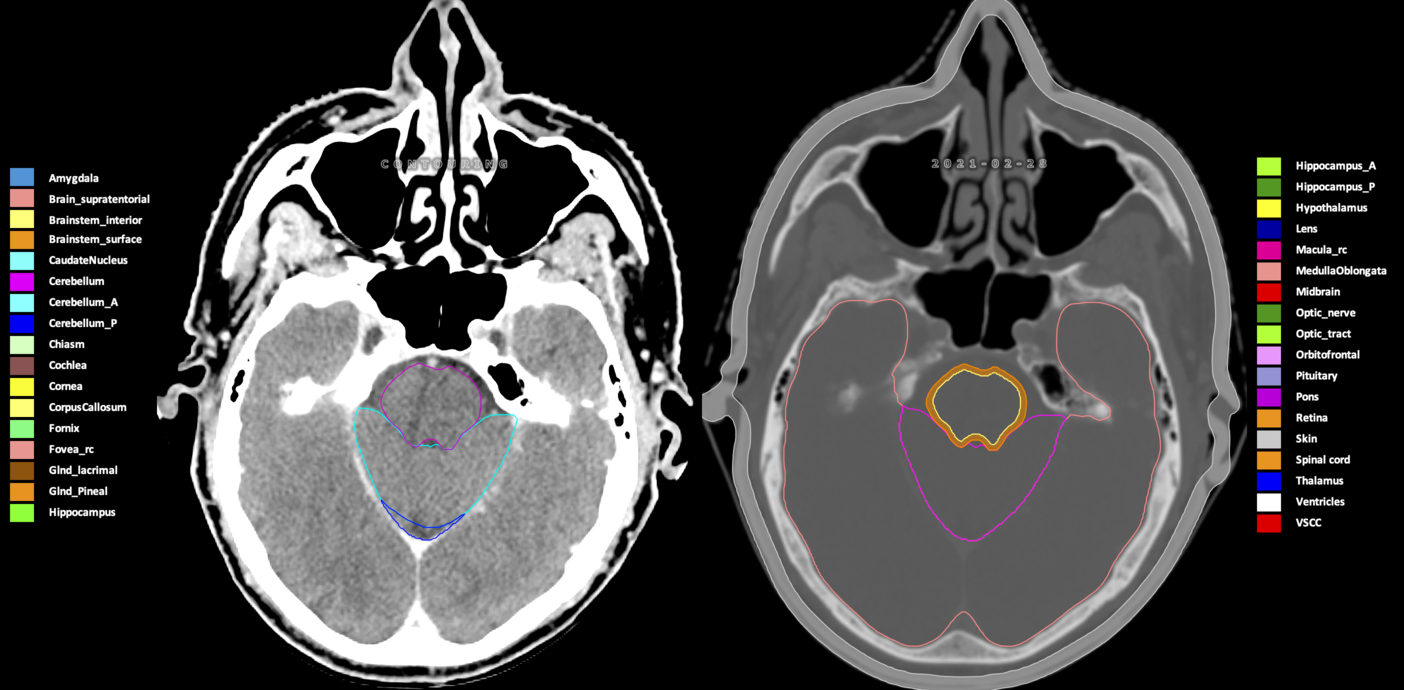

Included are all OARs known to be relevant for radiation-induced toxicity in neuro-oncology: brain, brainstem (midbrain, pons, medulla oblongata), chiasm, cerebellum (anterior & posterior), cochlea, cornea, hippocampus (anterior & posterior), hypothalamus, lens, lacrimal gland, optic nerve, pituitary, skin, and vestibular & semicircular canals. To further facilitate research on cognition, vision and radiological changes after irradiation of the brain, potential clinically-relevant OARs are included: amygdala, caudate nucleus, cerebellum (anterior & posterior), corpus callosum, fornix, macula, optic tract, orbitofrontal cortex, periventricular space (PVS), pineal gland, and thalamus.

Three-dimensional delineation of the 25 consensus OARs for neuro-oncology are shown on CT (WW/WL 120/40, 3000/600), 3T MR images, (T1Gd, T2FLAIR 1mm) and 7T MR (MP2RAGE 0.7 mm). All are presented in transversal, sagittal and coronal view.